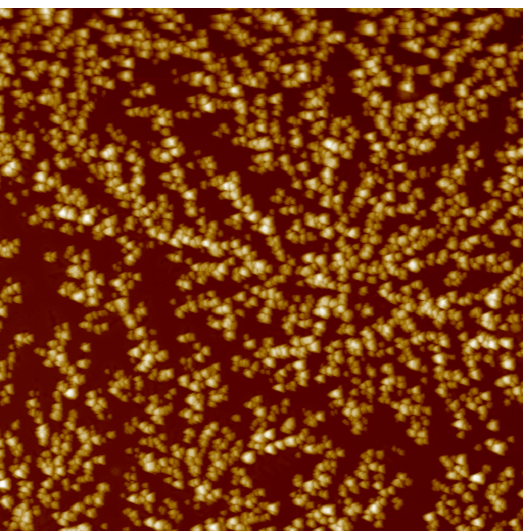

AFM scan of a dried tear from a diabetic patient

Diabetes

mellitus

Dense dendritic cores, thickened primary branches.